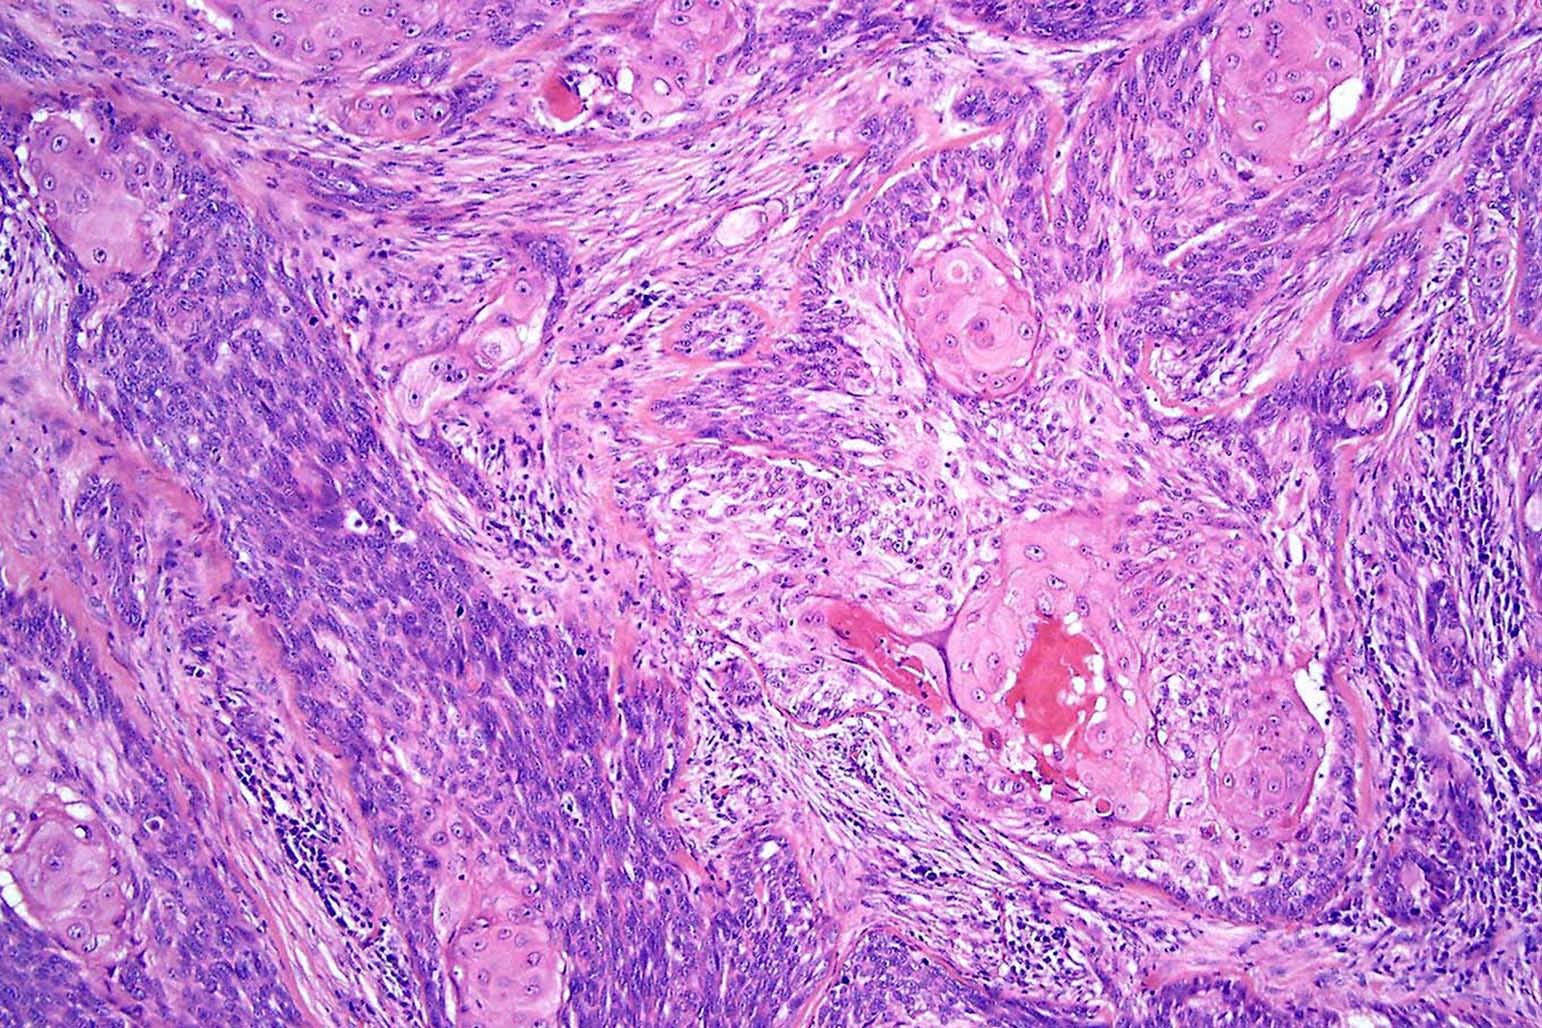

Common variants (Calonje: McKee's Pathology of the Skin, 5th Edition, 2019)

- Basosquamous (metatypical) BCC

- Biphasic tumor

- Foci of neoplastic squamous differentiation

Microscopic (histologic) images

Contributed by Antonina Kalmykova, M.D., Phillip H. McKee, M.D., Sate Hamza, M.D., Eduardo Calonje, M.D.,

Wayne Grayson, M.B.Ch.B., Ph.D., James Sampson, M.B.B.S., M.Sc. and Assia Bassarova, M.D., Ph.D.

- Squamous cell carcinoma (basaloid, clear cell, sarcomatoid):

- Shows an intraepidermal component, pagetoid spread

- No peripheral palisading, clefting or myxoinflammatory stroma

- Areas with conventional features like keratinization, keratin pearls

- BerEP4- (also absent in squamous areas of basosquamous carcinoma)